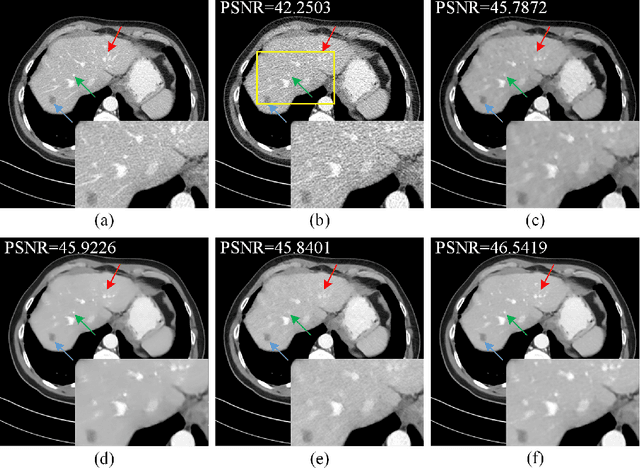

Abstract:Deep neural networks have a great potential to improve image denoising in low-dose computed tomography (LDCT). Popular ways to increase the network capacity include adding more layers or repeating a modularized clone model in a sequence. In such sequential architectures, the noisy input image and end output image are commonly used only once in the training model, which however limits the overall learning performance. In this paper, we propose a parallel-clone neural network method that utilizes a modularized network model and exploits the benefit of parallel input, parallel-output loss, and clone-toclone feature transfer. The proposed model keeps a similar or less number of unknown network weights as compared to conventional models but can accelerate the learning process significantly. The method was evaluated using the Mayo LDCT dataset and compared with existing deep learning models. The results show that the use of parallel input, parallel-output loss, and clone-to-clone feature transfer all can contribute to an accelerated convergence of deep learning and lead to improved image quality in testing. The parallel-clone network has been demonstrated promising for LDCT image denoising.